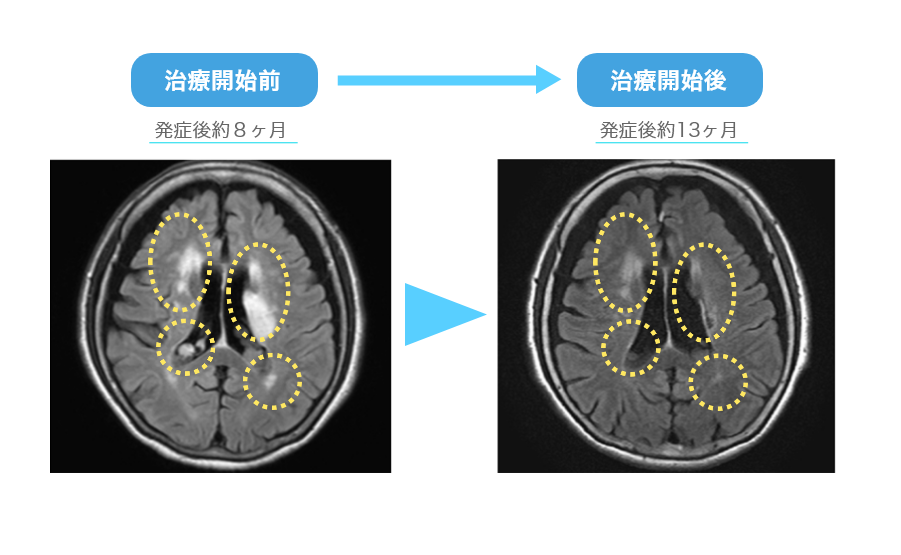

当院リニューロ®治療例:84歳女性 多発性脳梗塞

多発性脳梗塞治療開始前(発症後約8か月)と治療開始後(発症後約13か月)のMRI画像を比較しています。

白く映っている梗塞部位が縮小し、脳血流の改善が確認されました。※効果には個人差があります。